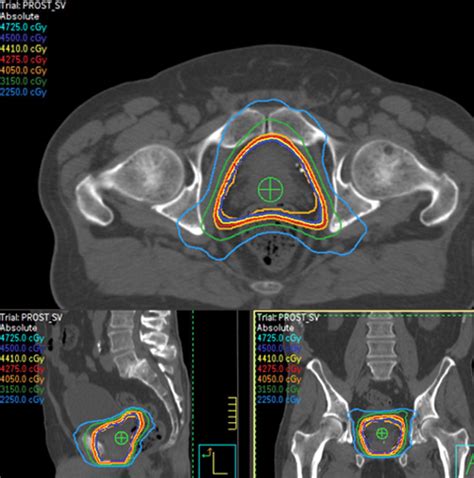

Why is lateralization so important in medical reports? Precision prevents medical errors and ensures that the correct tissue is being treated. For example, in radiation therapy, the delivery of high-energy beams must be perfectly calibrated to the "Rt" side to spare the healthy tissues on the opposite side. Surgeons also rely on this data to plan their incisions and lymph node dissections.

Modern imaging, such as PET-CT scans and MRIs, is the primary reason why we can be so specific about identifying Cancer At Rt. These technologies provide high-resolution images that allow radiologists to pinpoint the exact coordinates of a malignancy. When you review your scan results, look for these markers:

• Coordinates: Precise measurements of the mass's position within the organ.

• Involvement of Adjacent Structures: Whether the cancer has extended beyond the right-side boundary.

• Lymph Node Status: Often, clinicians look at the right axillary (for breast) or right hilar (for lung) lymph nodes to see if the condition has spread locally.